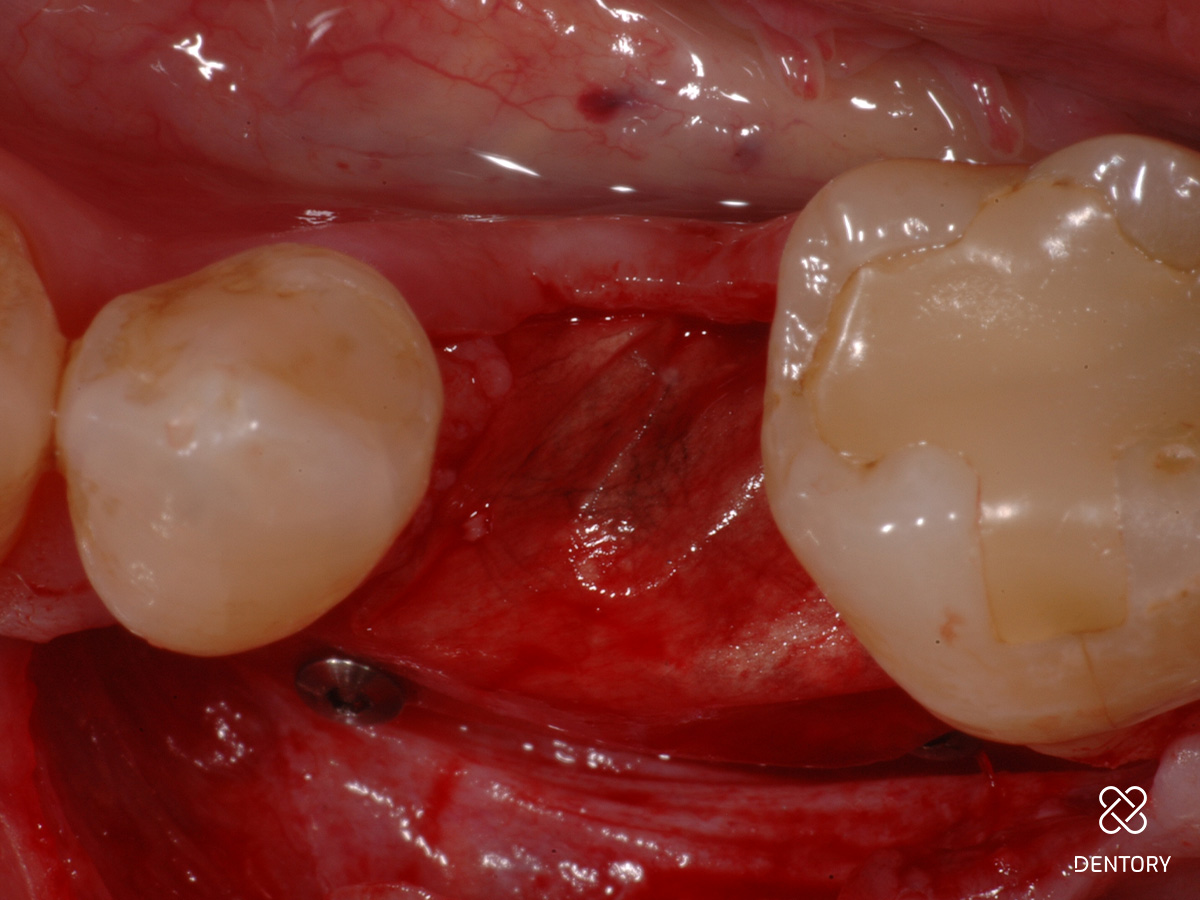

Abbildung 4

In der Lateralansicht zeigt sich ein moderater Dehiszenzdefekt bei gut erhaltener Knochenstruktur an den Nachbarzähnen, welche die Knochenregeneration unterstützen werden.